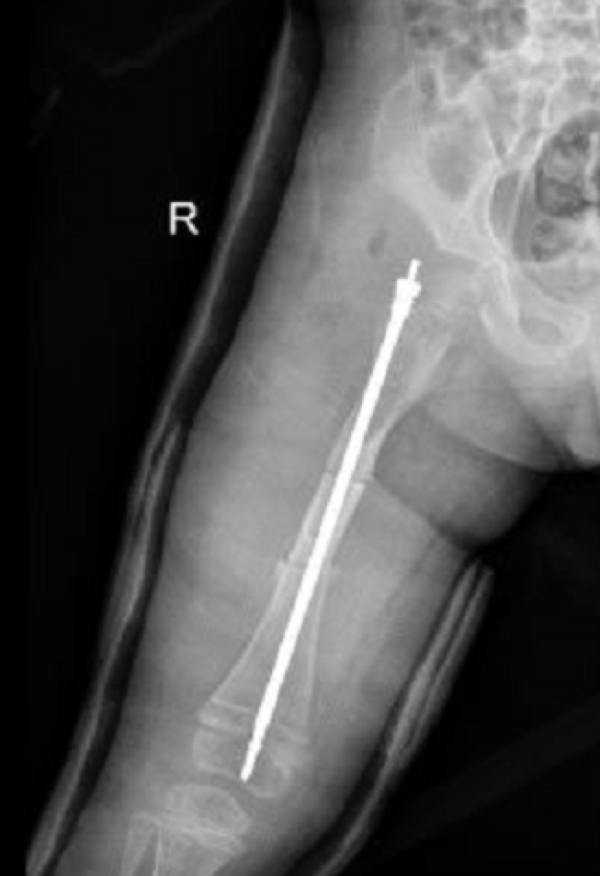

壮壮股骨内的可延长髓内钉 医院供图

近日,壮壮在浙江大学医学院附属儿童医院进行了一起省内首例手术:在股骨骨髓腔内,放置可延长髓内钉,增加骨头牢度。当孩子长高时,髓内钉也会慢慢变长,一直保护着他的骨骼。

“放置可延长髓内钉,一是治疗本次骨折,二是纠正前几次骨折残留的股骨畸形,三是有效避免将来再次骨折,为孩子脆弱的骨头加一层保护。”陈建松介绍。

术前,骨科团队仔细测量了孩子股骨的各项数据,准备了合适的可延长钉,制定了精准的手术方案,经过2个小时的密切配合,手术顺利完成。按照预期,术后一周壮壮便可以出院,一个半月后拆石膏,在床上开始活动关节,三个月后就可以慢慢下地走路。